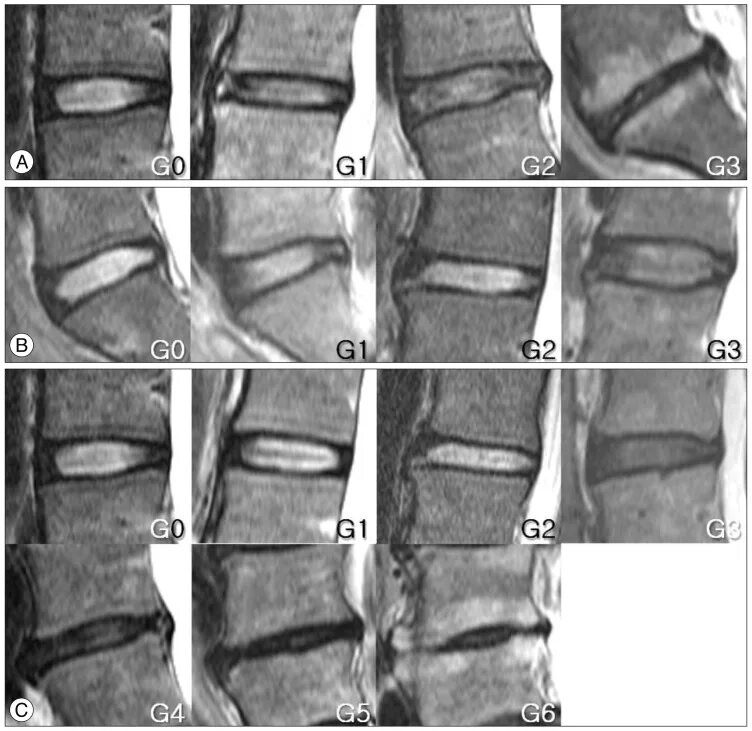

Дегенерация межпозвонкового диска по pfirrmann